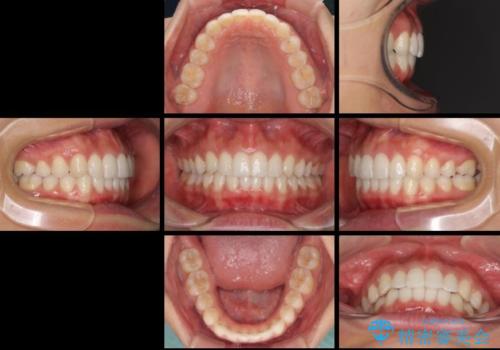

1日22時間の装着時間をしっかり守ってくださったので、予定通り1年で治療を終えることができました。

ディープバイトによる食いしばり癖も解消され、患者様には大変満足していただきました。